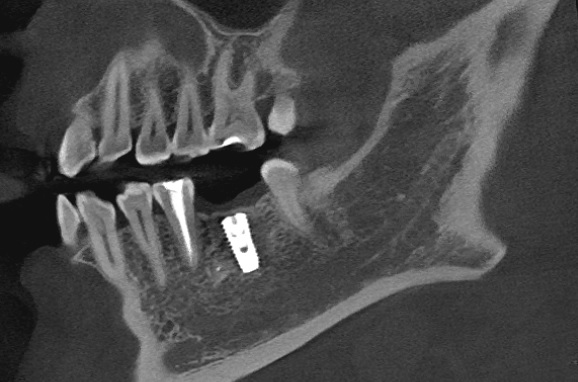

- Провели 3Д КТ обследование 2500 ₽.

- После внимательного изучения 3Д КТ снимков пациентке предложено провести имплантацию корейской системой OSSTEM, средней ценовой категории, с установкой коронки из диоксида циркония.

- Установка импланта системы Implantium 33 000 ₽.

- Изготовление коронки на имплант из диоксида циркония с винтовой фиксацией 42 000 ₽